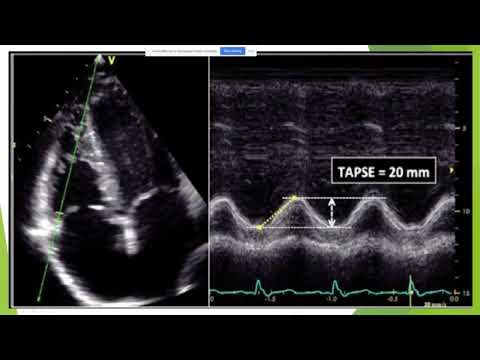

The Notebook 7 Chapter IV: The Transthoracic Echocardiogram In This Chapter We Identify the Cardiac Sonographer’s role prior to the TTE, including paperwork, patient positioning, & scanning options. Apply the steps of the TTE, including 2D, M-mode, & Doppler of all the views incorporating the cardiac dimensions and routine calculations of the cardiac anatomy; Better understand & recognize the cardiac anatomy and interpret the findings; Acquire & interpret the updated LV diastolic function parameters; as well as an introduction to RV diastolic function; Although no longer recommended, recognize, define, & acquire the M-mode dimensions.